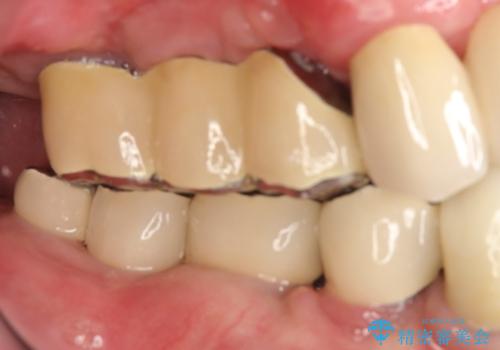

虫歯だらけ、歯周病 崩壊した口腔の再建 フルマウスリコンストラクション

かみ合わせの力が非常に強く、夜間の歯ぎしり・食いしばりもひどかったため、奥歯はメタルオクルーザルの設計でかぶせ物を製作しています。

かぶせ物の種類:PFZ / PFM metal occlusal